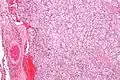

Micrograph of a carotid body tumor

The paragangliomas appear grossly as sharply circumscribed polypoid masses and they have a firm to rubbery consistency. They are highly vascular tumors and may have a deep red color.

On microscopic inspection, the tumor cells are readily recognized. Individual tumor cells are polygonal to oval and are arranged in distinctive cell balls, called Zellballen.[8] These cell balls are separated by fibrovascular stroma and surrounded by sustentacular cells.

By light microscopy, the differential diagnosis includes related neuroendocrine tumors, such as carcinoid tumor, neuroendocrine carcinoma, and medullary carcinoma of the thyroid.

With immunohistochemistry, the chief cells located in the cell balls are positive for chromogranin, synaptophysin, neuron specific enolase, serotonin, neurofilament and Neural cell adhesion molecule; they are S-100 protein negative. The sustentacular cells are S-100 positive and focally positive for glial fibrillary acidic protein. By histochemistry, the paraganglioma cells are argyrophilic, periodic acid Schiff negative, mucicarmine negative, and argentaffin negative.